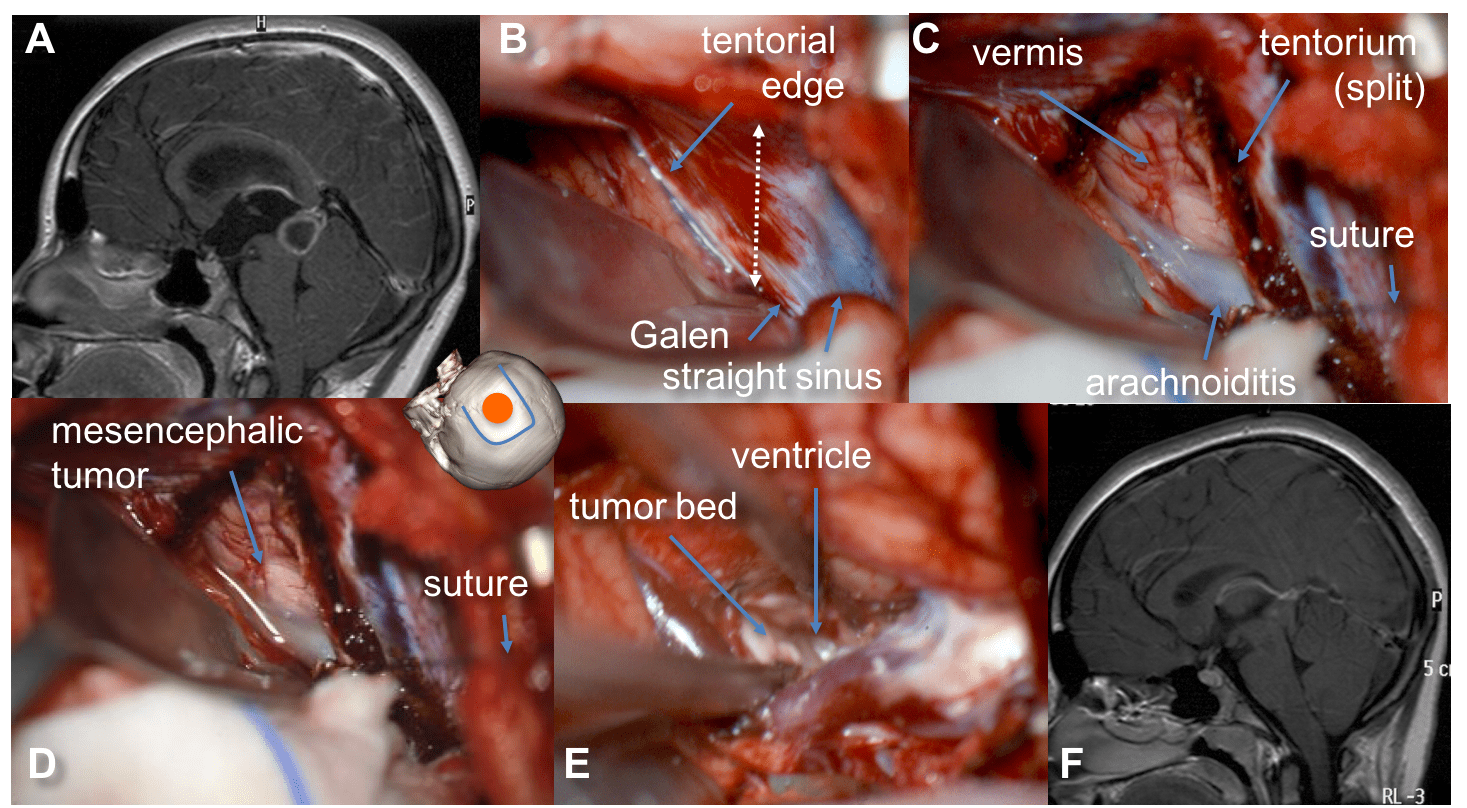

A: bone flap and dural incision (dotted line); B: exposition of the tectorial edge - à l’ouverture durale, le pôle occipital sort sous pression, il se détend après soustraction de LCS dans la citerne ambiente.

- ouverture de la tente du cervelet parallèle au sinus droit et rétraction par sutures, exposant la pointe du vermis et la citerne quadrijumelle ; hémostase des veines de la tente par bipolaire, tamponnement, hémoclips

A: tectal plate tumor; B: exposition of the tectorial edge; C: splitting of the tentorium parallel to the straight sinus, exposing the vermis and quadrigeminal cistern; D: cisternal dissection of the tumor limits; E: after tumor resection, the tumor bed and the posterior third ventricle are exposed. - dissection cisternale : souvent arachnoïdite dense

- dissection des éléments du carrefour veineux : veine basale, Galien, pré-centrale ; la dissection de la veine basale permet d’exposer le pulvinar.

- sacrifice de la veine pré-centrale par hémoclips, coagulation (parfois clip d’anévrysme si l’abord est trop exigu pour les hémoclips) : donne accès à la face opposée de la tumeur pinéale ou à la tumeur tectale, et à la face supérieure de la tumeur en suivant les veines cérébrales internes.

A: exposition of the tectal tumor after splitting of the tentorium; B: section of the precentral vein allowing access to the tectal plate and third ventricle - la tumeur est disséquée des veines adjacentes, en particulier les veines cérébrales internes auxquelles elle peut adhérer (tératomes résiduels après chimiothérapie)